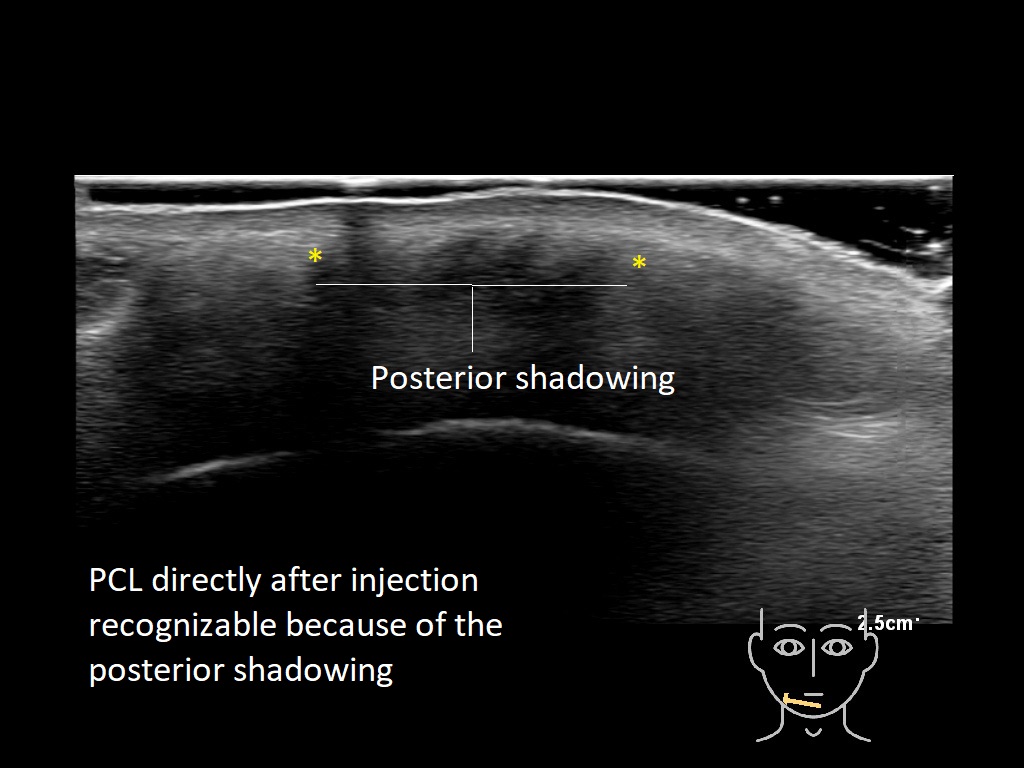

Fillers

Draw in the second image below where the fillers are located. To check if your answer is correct, swipe the first image to the right.

PCL 0